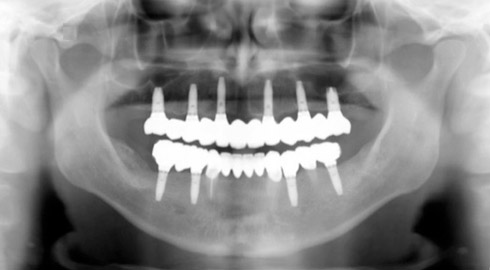

Exemple d’une réhabilitation complète implantaire

Situation clinique initiale

Situation clinique terminée